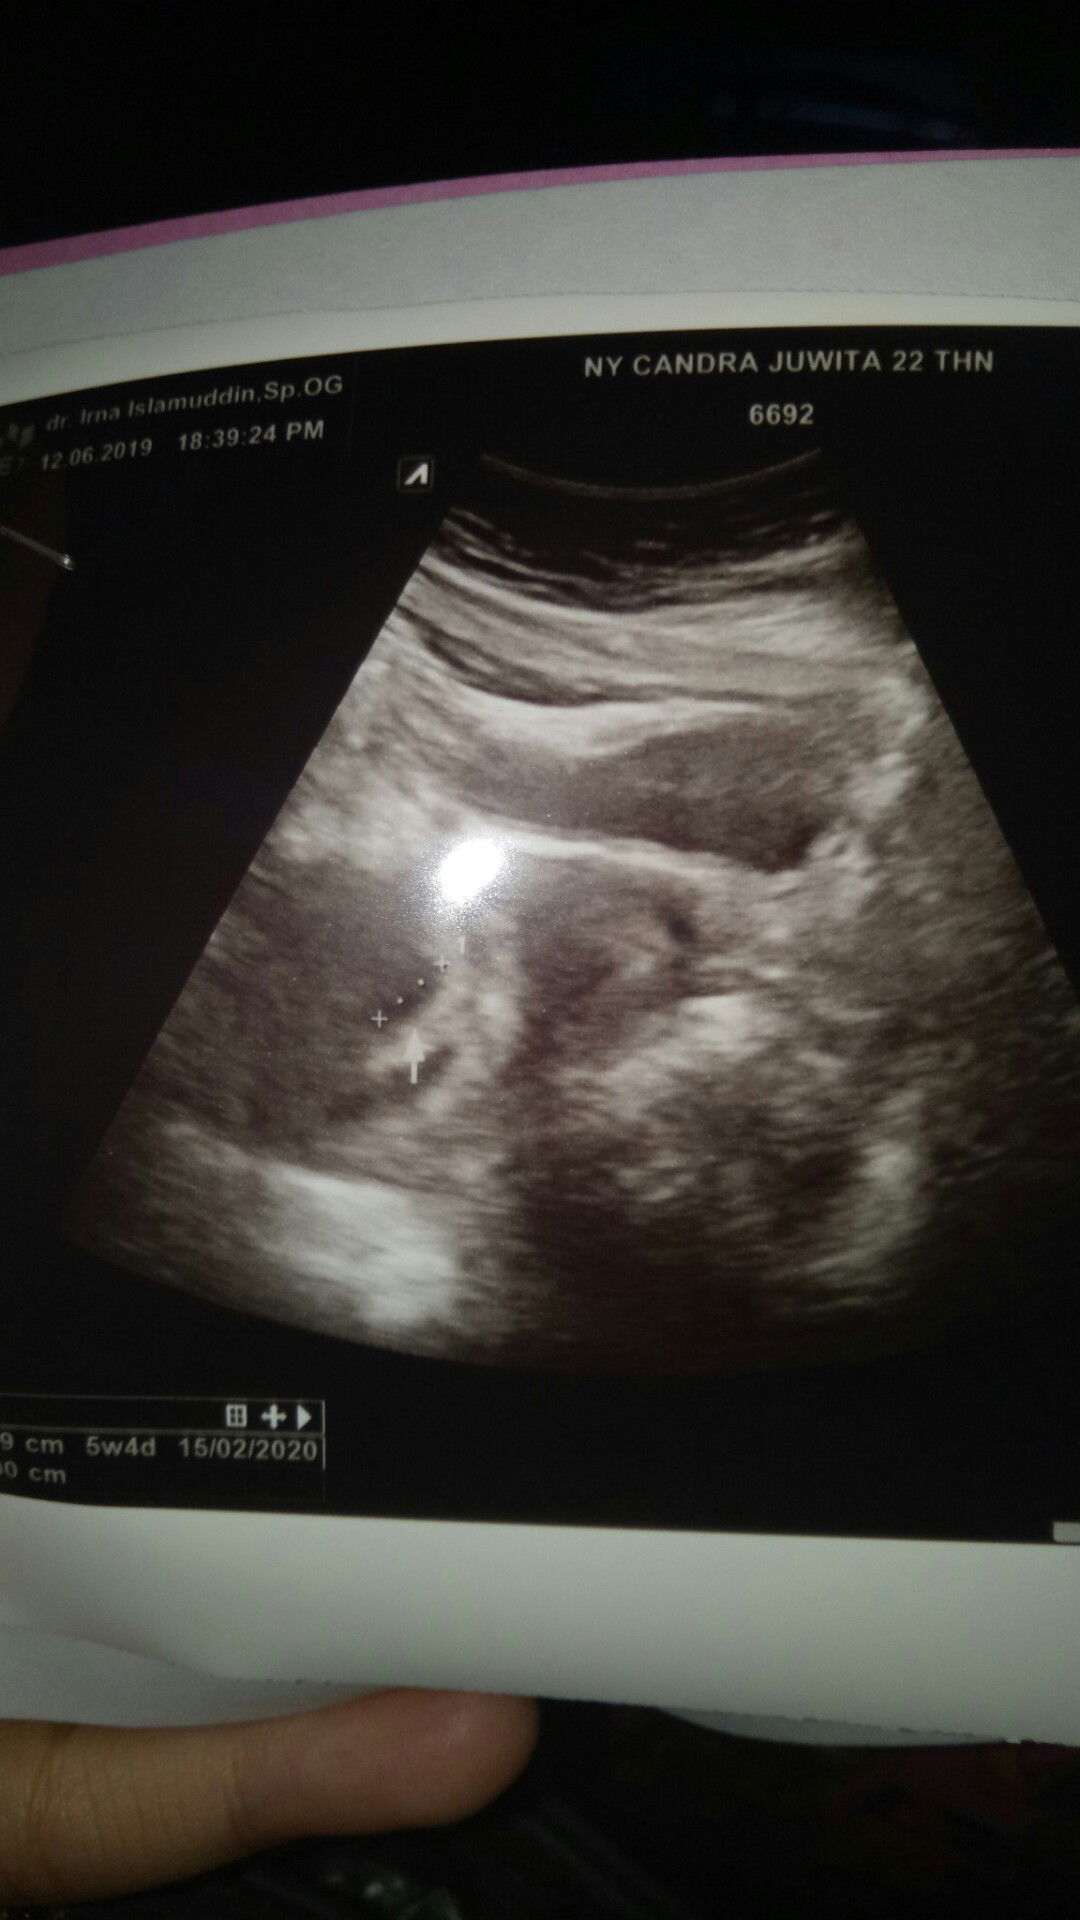

Ada yg pernah gak? Klo dihitung dri hpht misalkan usia kehamilannya 5minggu 6hari tpi pas usg masih 5minggu 4 hari kayak gtu,beda duahari? Ini hasil usg aku brusan, kata dokternya sih bru kantong doang yg kelihatan,jdi dsuruh blik lagi 2 minggu kemudian, ada yg pernah usg 5 minggu dh kelihatan janinnya?